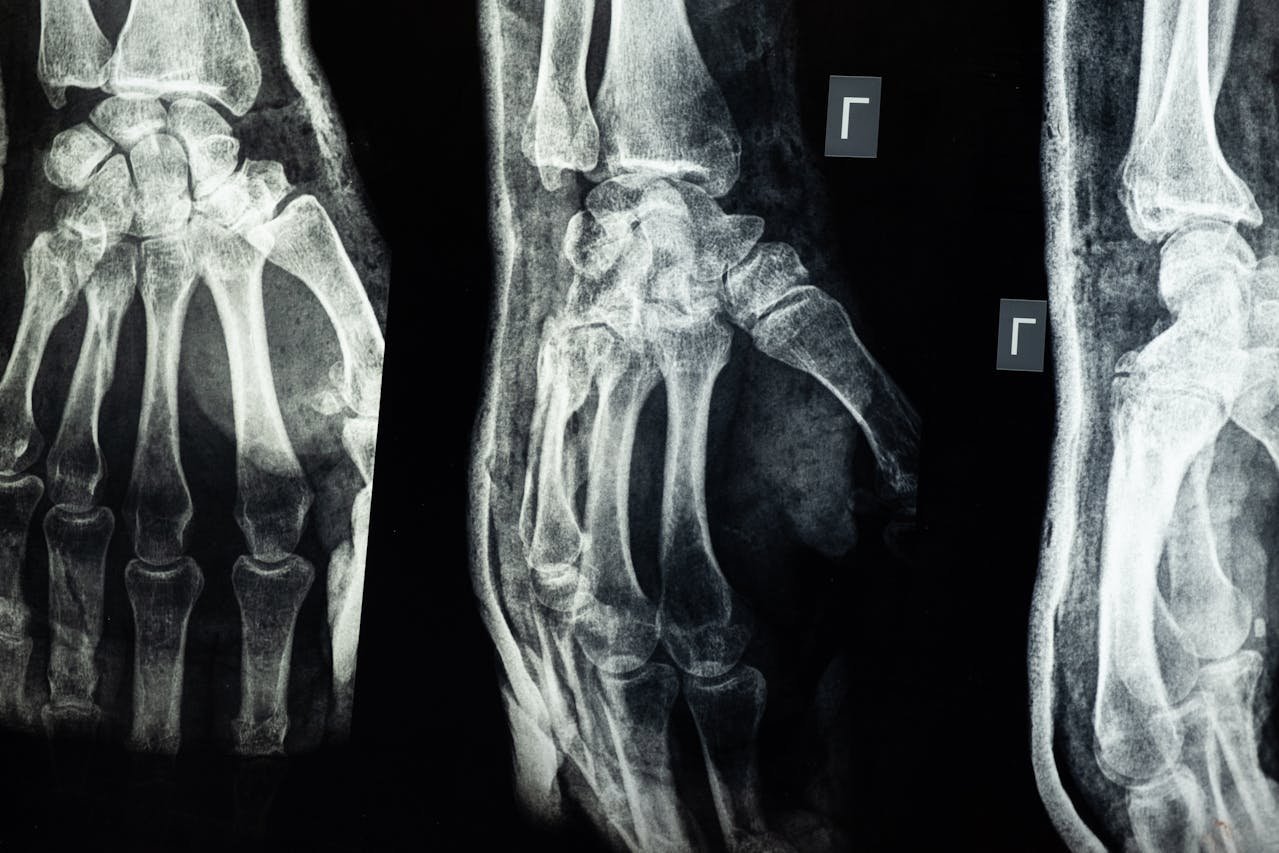

There are many different types of fractures. Some fractures, such as greenstick fractures, happen mostly in children, while others, such as compression fractures, are more common in adults. Each type of fracture has its own different type of management, including physiotherapy. Some of the common types of fractures are listed below:

- Comminuted fracture: This type of fracture happens when the bone is completely shattered into various pieces. This fracture often takes significantly longer to heal than other fractures.